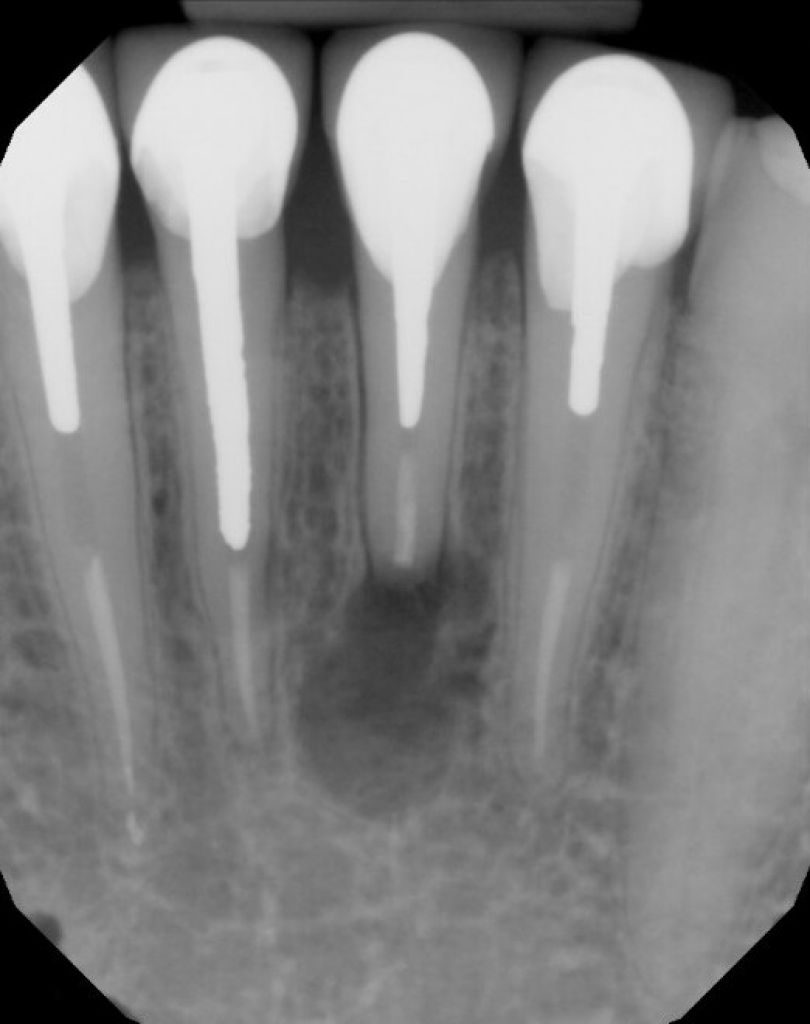

#9 S-RCT

Dx: Previously Treated with SAP